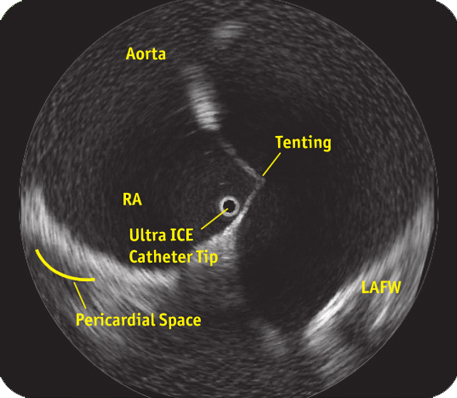

ULTRA ICE™ PLUS ULTRASOUND IMAGING CATHETER

Unique Vision:360°view of the world

トランスデューサーが回転し、360°パノラマ画像が作成されます